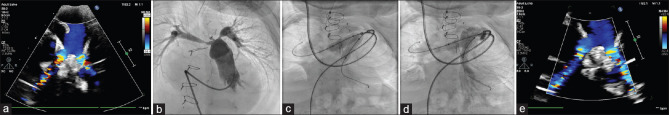

Background: Branch pulmonary artery (PA) stenosis must be addressed early to prevent right ventricular scarring and establish lung blood flow. Balloon-mounted stents are more useful in managing right ventricular outflow tract (RVOT) obstruction and PA stenosis.

Materials and methods: We studied the clinical and angiographic data of children with congenital heart disease who underwent stenting for RVOT obstruction and branch PA stenosis using the Formula stent (Cook Medical, Limerick, Ireland) between 2018 and 2024 in a tertiary pediatric cardiac center in southern India.

Results: Our patient cohort included 65 patients with a median age of 3 years (range: 3 months to 17 years). The median weight of patients was 11.5 kg (4.8-60.4 kg), with 40% weighing <10 kg. Out of the 87 stents implanted, four stents were implanted in RVOT, while the rest were branch PA stenting. The median stent length was 20 mm (12-60 mm), and the median stent diameter was 10 mm (5-10 mm). All stents were deployed using 5Fr to 8Fr sheaths or guiding catheters. The median procedure time was 62 min (20-170 min), with a median fluoroscopy time of 15 min (4-110 min). A total of 17 (19%) stents in 14 patients required further dilatation at a mean interval of 25 ± 4 months from the time of stenting. Ballooning resulted in an increase in diameter from 7.8 ± 2.2 mm to 10.2 ± 1.7 mm. Right ventricular systolic pressure had reduced from 70.3 ± 8 to 40.1 ± 1 mmHg after balloon dilatation in patients with a biventricular heart.

Conclusion: The Formula stent provides a comprehensive stent size option, requiring smaller sheaths, reduced procedural time, minimum complications, and an acceptable rate of reinterventions.